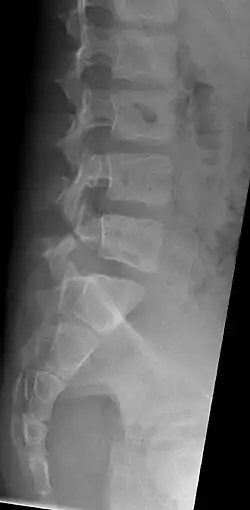

Als Spondylolysis oder Spondylolyse bezeichnet man die Unterbrechung der Pars interarticularis (Interartikularportion, der Bereich zwischen oberem und unterem Gelenkfortsatz) im Bogen meist des fünften (80 % der Fälle) oder vierten Lendenwirbels (15 % der Fälle).

Als Folge der Spondylolysis ist die Mobilität des Wirbelsegments erhöht, was zu asymmetrischem Wachstum der Grund- und Deckplatten und somit zur Entwicklung eines Wirbelgleitens (Spondylolisthesis) führen kann. In seltenen Fällen führt die Spondylolysis zum völligen Abrutschen des Wirbelkörpers (Spondyloptose).